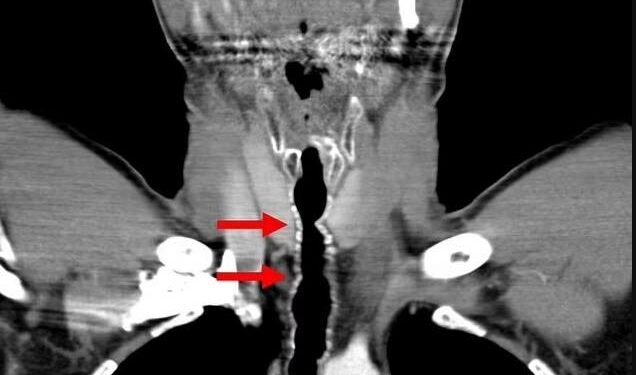

صورة ترمز الى المنطقة التي نبت فيها الشعر

وعندما خضع لتنظير القصبات، تبيّن للطبيب المعالج وجود التهاب وعدة شعرات في حلق هذا الرجل. وبالفعل تمكّن الفريق الطبي المساعد من إزالة الشعر عن طريق نتفه، وهو إجراء قدّم راحة مؤقتة للمريض الذي استمر الشعر في النمو بعد ذلك، ما استدعى عودته إلى المستشفى سنوياً لمدة 14 عاماً، لعلّه يتمكّن من القضاء على الأعراض التي يعانيها.

وبحسب الصحيفة، فإن عدد الشعرات في حلق هذا الرجل، تتراوح بين 6 و9 شعرات يبلغ طولها 5 سنتيمترات. والملفت أن بعضها يمرّ عبر الحنجرة وينمو في فمه!